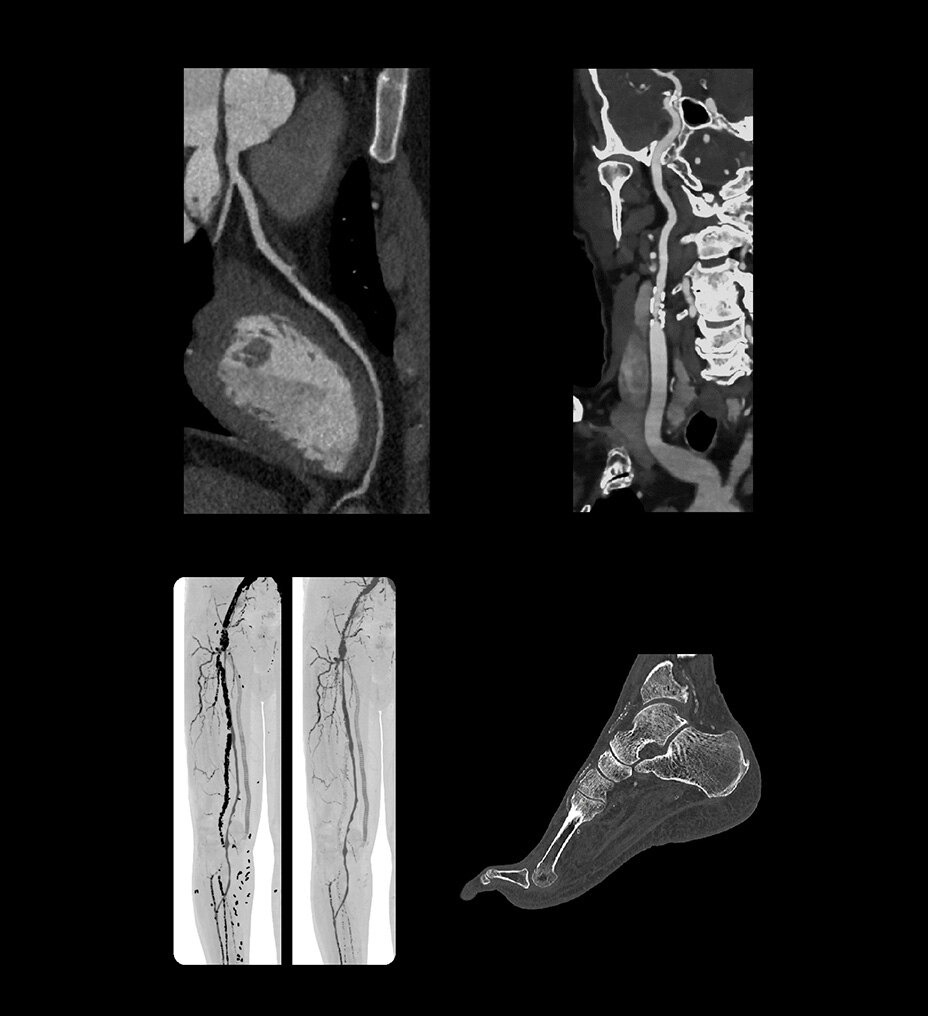

SIGNA™ Champion offre un design modulare con opzioni software e hardware pronte per soddisfare le priorità cliniche. Include strumenti di base e avanzati e soluzioni per la qualità delle immagini come AIR™ Recon DL e Sonic DL™. Queste applicazioni consentono non solo di ottimizzare i casi di routine, ma anche di operare in altri campi specifici come neurologia, apparato muscolo-scheletrico, cardiologia e oncologia. E non è tutto. SIGNA™ Champion è in grado di offrire configurazioni a 32, 48 e 64 canali per garantire la massima flessibilità e semplificare la configurazione delle bobine sulla base delle diverse anatomie.